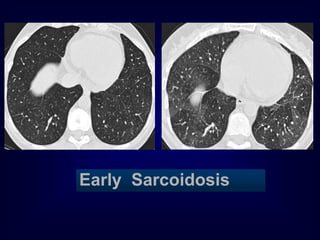

Sarcoidosis

Early Sarcoidosis